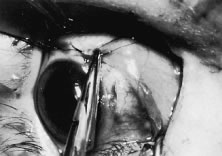

Another common source of hemorrhage is bleeding from the anterior ciliary vessels. This bleeding may occur when a needle is passed through the tendon and penetrates one of the anterior ciliary vessels. This penetration will cause a self-limited hematoma under the muscle capsule (Fig. 75). It may also occur when the Tenon's tissue is cleaned from the muscle (Fig. 76). Hemorrhage around the insertion may make removal of the muscle from the globe difficult because it can obscure the area where the tendon of the muscle is attached to the globe. Bleeding from the anterior ciliary vessels can be controlled by cauterizing vessels with a wet-field (bipolar) cautery. Care should be taken not to cauterize tissue near a suture after it has been placed because doing so may cause structural damage to the suture.

Fig. 75. A small hematoma in the muscle capsule resulted from cutting the anterior ciliary vessel when cleaning the muscle insertion before placing the suture.

Fig. 76. The muscle capsule has been removed from the muscle tendon. Hemorrhage can occur, which can obscure the surgical field.